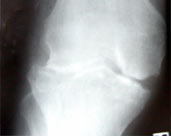

Koch's knee arthritis preop xray lat

Koch's knee arthritis preop

Koch's knee arthritis preop xray ap